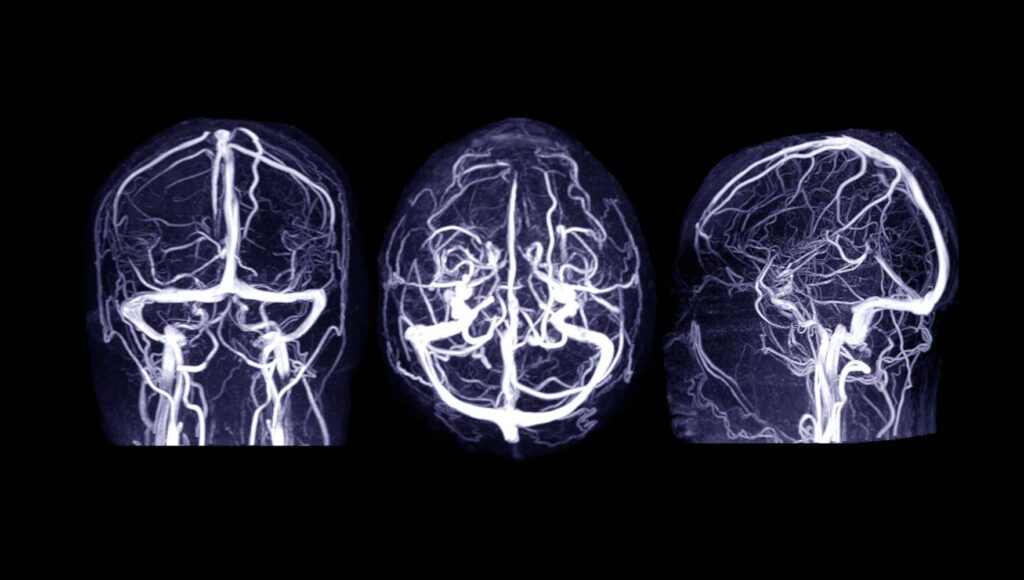

Die MRT-Phlebografie basiert prinzipiell auf der Methode der Magnetresonanztomographie (MRT). Dabei werden Schnittbilder des Körperinneren mittels starker Magnetfelder und Radiowellen angefertigt – also gänzlich ohne den Einsatz von Röntgenstrahlung. Diese zweidimensionalen Bilder können anschließend am Computer übereinandergelegt werden, wodurch ein dreidimensionaler Eindruck entsteht. So können die Venen in ihrem gesamten Verlauf dargestellt werden.

Bei der MRT-Phlebografie unterscheidet man die direkte Darstellung von der indirekten Phlebografie. Bei der direkten Methode wird zunächst eine Fußvene punktiert, über die in der Regel ein gadoliniumhaltiges Kontrastmittel gespritzt wird. Anschließend werden MRT-Aufnahmen angefertigt. Das sich das Kontrastmittel in den Venen anreichert, erscheinen diese auf den MR-Aufnahmen dann deutlich heller als die umliegenden Gewebe. So lassen sich die Gefäße einerseits gut abgrenzen und andererseits werden so – durch eine Kontrastmittelaussparung – auch etwaige Thrombosen sichtbar.

Die MRT ist eine hochpräzise Untersuchungstechnik, weshalb nicht nur größere Auffälligkeiten sichtbar werden, sondern sich auch bereits kleinste Veränderungen sicher erkennen lassen. Schließlich kann durch spezielle Computerprogramme auch ein dreidimensionaler Datensatz erzeugt werden, bei dem die umliegenden Gewebe entfernt werden, sodass ausschließlich die Gefäße gezeigt werden. So können diese isoliert vom Rest des Körpers bis ins letzte Detail beurteilt werden.

Bei der indirekten MRT-Phlebografie hingegen ist die Gefäßdarstellung gänzlich ohne Kontrastmittel inzwischen möglich. Durch verschiedene spezielle MRT-Methoden können physikalische Eigenschaften und Unterschiede des Blutes genutzt werden, um eine kontrastverstärkte Darstellung der Gefäße zu erreichen.